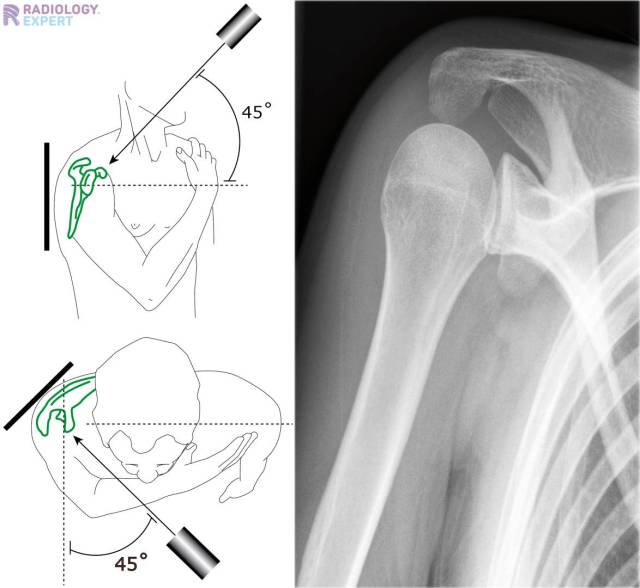

X Ray Shoulder Oblique View . Normal ap oblique shoulder radiograph. The thin body of the scapula should be seen on end without rib superimposition. Provides better detail of cortical and trabecular bone structures than mri at cost of higher radiation exposure. A defect in the rim of the glenoid is also present (arrow). Normal ap oblique internal rotation view (grashey view). This apical oblique view shows the abnormal articular surface of the humeral head with a fragment (arrowhead) adjacent to it; It is also known as a true ap view since. The shoulder series is fundamentally composed of two orthogonal views of the glenohumeral joint including the entire scapula. There for optimal for visualization of bony defects. The body has to be rotated about 30 to 45 degrees towards the shoulder to be imaged, and the standing or sitting patient lets the arm hang. A true lateral view of the scapula, proximal humerus, and scapulohumeral joint.

X Ray Shoulder Oblique View Normal ap oblique shoulder radiograph. The thin body of the scapula should be seen on end without rib superimposition. A true lateral view of the scapula, proximal humerus, and scapulohumeral joint. This apical oblique view shows the abnormal articular surface of the humeral head with a fragment (arrowhead) adjacent to it; A defect in the rim of the glenoid is also present (arrow). The shoulder series is fundamentally composed of two orthogonal views of the glenohumeral joint including the entire scapula. Normal ap oblique shoulder radiograph. It is also known as a true ap view since. Provides better detail of cortical and trabecular bone structures than mri at cost of higher radiation exposure. Normal ap oblique internal rotation view (grashey view). The body has to be rotated about 30 to 45 degrees towards the shoulder to be imaged, and the standing or sitting patient lets the arm hang. There for optimal for visualization of bony defects.